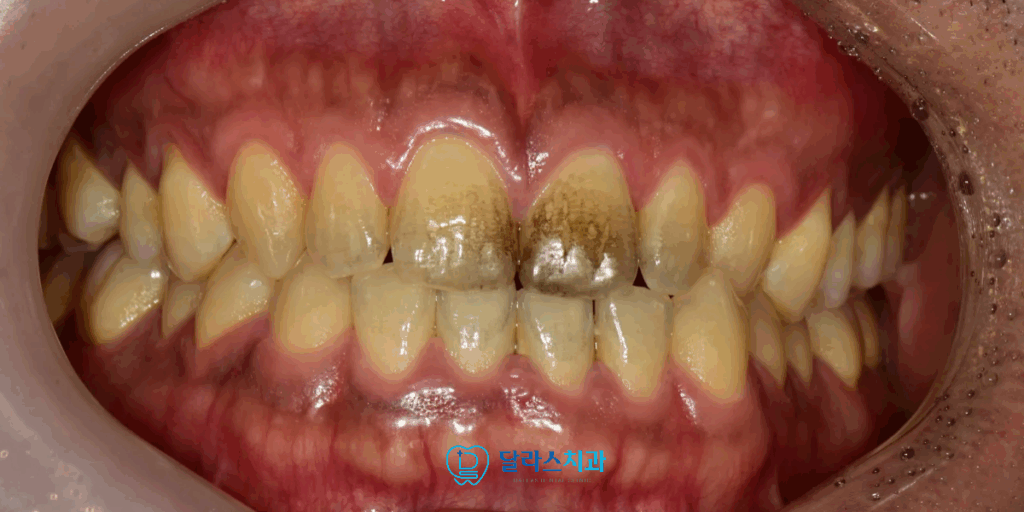

이번에 저희 노원치과 달라스치과를 내원하신 환자분은

30대 남성으로 전자 담배 사용으로 인해

치아 표면에 광범위한 착색이 생겨 인터넷을 통해

AirFlow가 효과적이라는 정보를 접하시고 내원하셨습니다.

노원치과 내원 당시 치아 표면은 일반적인 스케일링만으로는

제거가 어려운 정도의 넓은 범위의 착색이 확인되었습니다.

보통 착색은 다양한 부위에서 발생하는데

환자분의 경우 전자담배 연기와 많이 접촉을 하는

앞니 쪽에 착색이 광범위하고 진하게 발생하여서

심미적으로도 매우 보기가 좋지 않았습니다.

또한 입안쪽으로는 잇몸 경계부분을 따라서 착색이 진행되어 있었습니다.